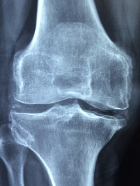

무릎 퇴행성 관절염 원인

무릎 퇴행성 관절염의 정확한 원인은 아직 밝혀지지 않았지만, 여러 요인이 복합적으로 작용하는 것으로 생각됩니다. 일반적으로 노화에 따라 연골의 수분 함량이 감소하고 탄력성이 떨어져서 손상되기 쉬워지는 것이 주요 원인입니다. 그 외에도 다음과 같은 요인들이 무릎 퇴행성 관절염의 위험을 증가시킬 수 있습니다.

- 유전: 가족력이 있는 경우 무릎 퇴행성 관절염에 걸릴 확률이 높습니다. 특히 여성의 경우 어머니가 이 질환을 가지고 있다면 자녀도 그렇게 될 가능성이 큽니다.

- 체중: 과체중이나 비만인 경우 무릎에 부담이 가해져서 연골이 손상될 수 있습니다. 체중 1kg당 무릎에 가해지는 압력은 4kg에 달한다고 합니다.

- 외상: 스포츠나 사고 등으로 인해 무릎에 부상을 입은 경우 연골이 손상되거나 염증이 생길 수 있습니다. 특히 반복적인 외상은 연골의 재생을 방해하고 퇴행을 촉진할 수 있습니다.

- 직업: 오랫동안 서서 일하거나 무릎을 굽힌 자세로 일하는 경우 무릎에 과도한 스트레스가 가해져서 연골이 마모될 수 있습니다. 예를 들어 건설, 청소, 운송, 군인 등의 직업군은 무릎 퇴행성 관절염의 위험이 높습니다.

- 기타 질환: 당뇨병, 갑상선 기능 저하증, 통풍, 결핵, 골다공증 등의 질환을 가진 경우 무릎 퇴행성 관절염에 걸릴 확률이 높아집니다. 이러한 질환들은 연골의 영양 공급을 방해하거나 염증 반응을 유발하여 연골을 약화시킬 수 있습니다.